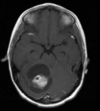

Q

35 anos, Masculino

A

Craniofaringioma adamantinomatoso

Craniofaringioma adamantinomatoso Crianças Lesão suprasselar com componente sólido e cístico; lobulado; calcificação anelar ou nodular presente em quase TODOS os craniofaringeomas pediátricos; Componente cístico proeminente e componente sólido pequeno, mas com realce.